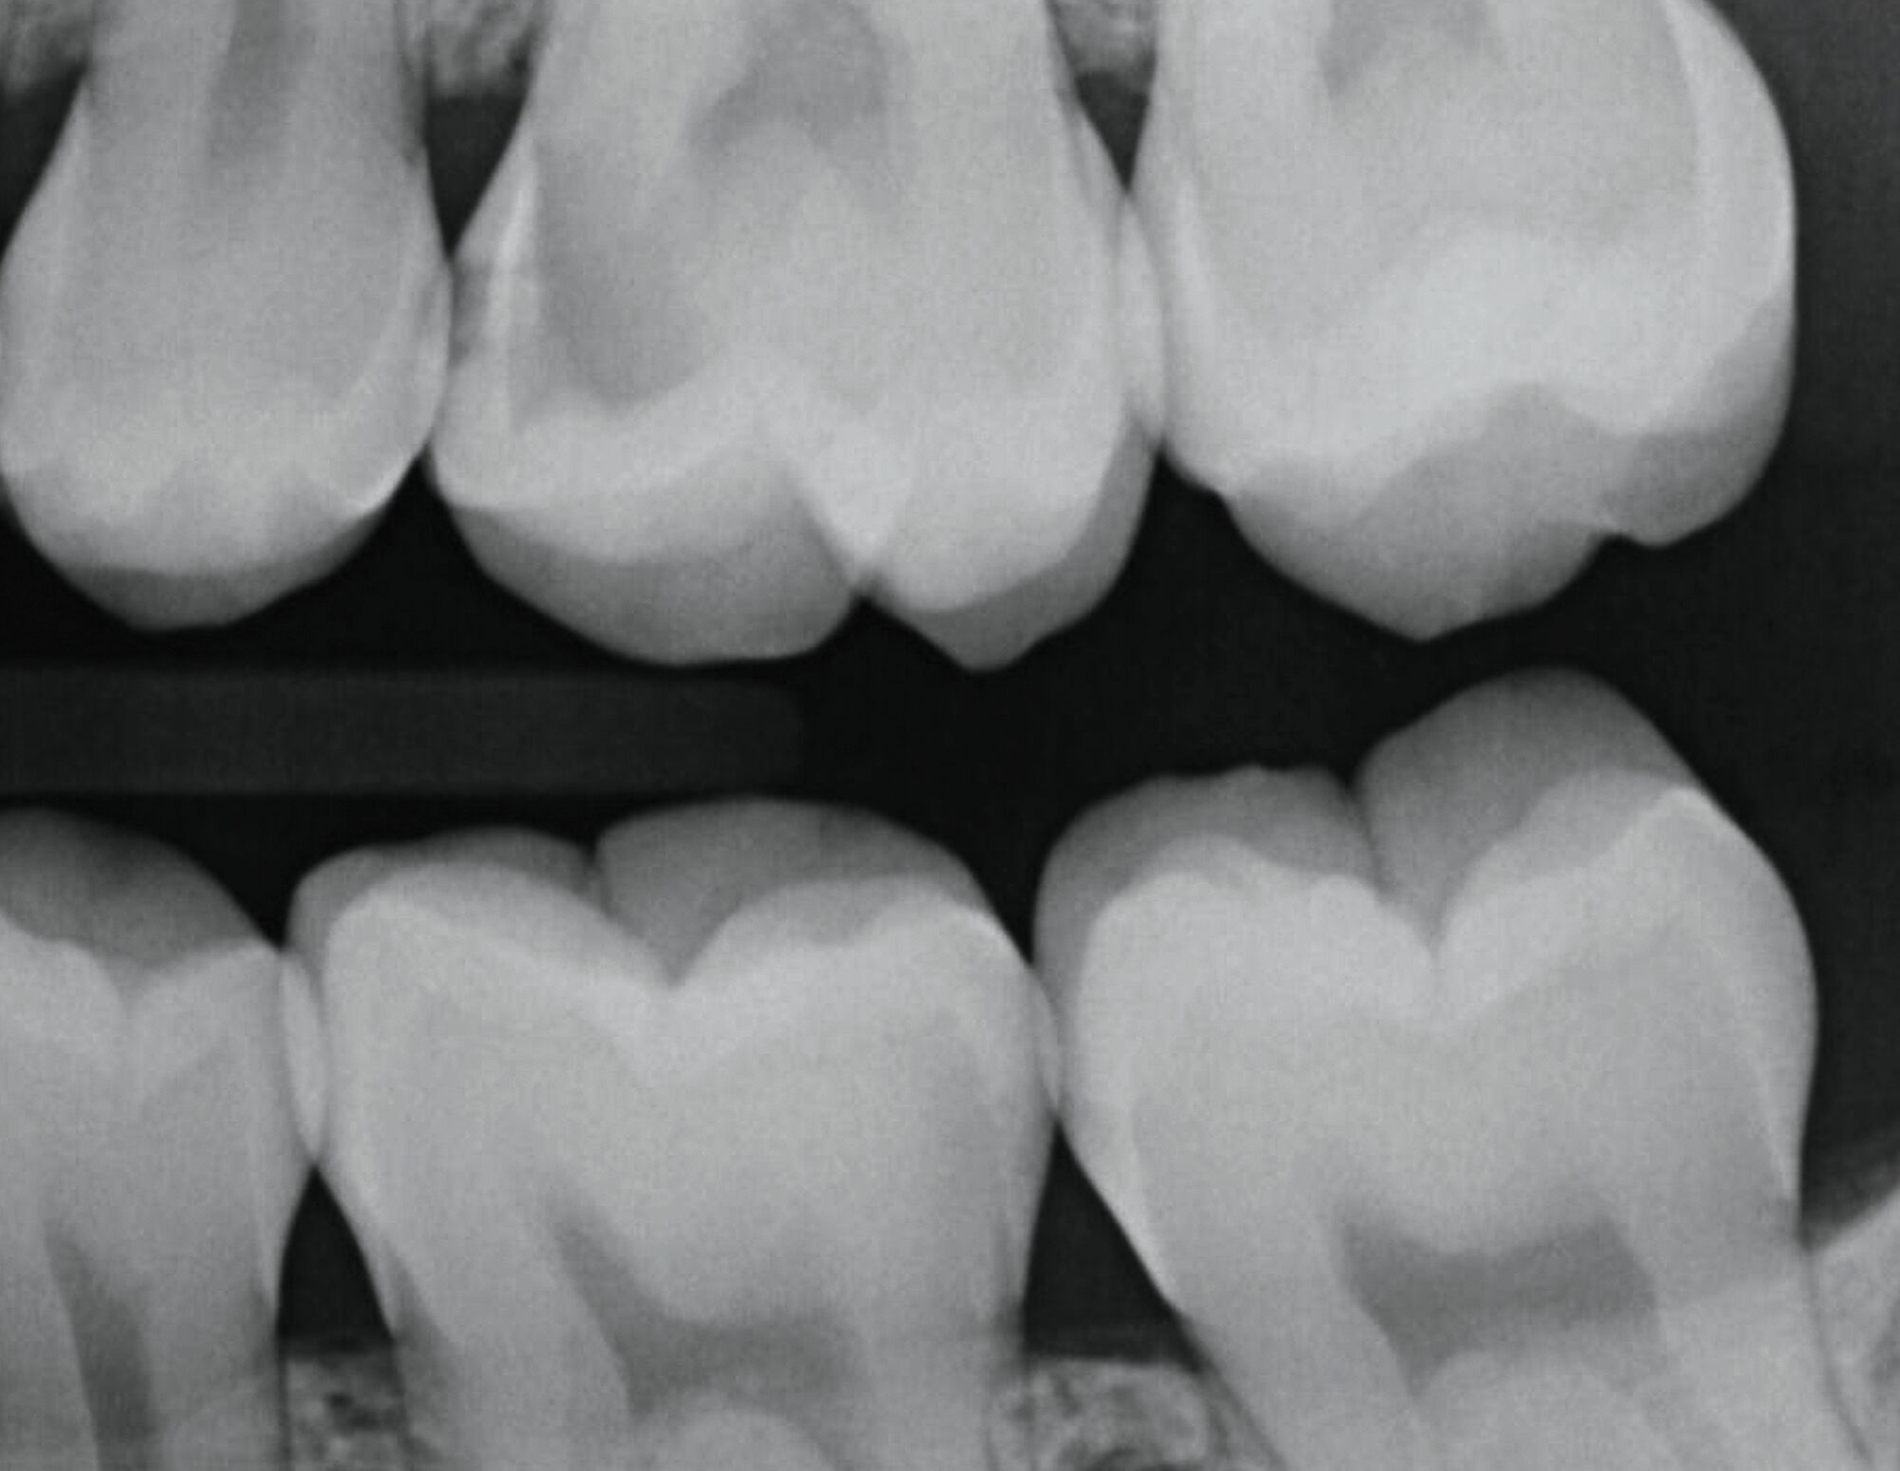

Die pulpanahe Karies im Praxisalltag

Sicherlich haben Sie schon öfter ähnliche Situationen erlebt: Der Patient stellt sich mit leichten Zahnschmerzen vor und nach der Befunderhebung stellen Sie kariöse Läsionen fest, die sich radiologisch als pulpanah erweisen. Es braucht vermutlich gar nicht viel Erfahrung, um abzusehen, dass die vollständige Kariesentfernung nach klassischen Kriterien hier zu einer Pulpaeröffnung führen würde. Das Ziel ist klar: Die Pulpa soll vital bleiben. Doch welcher Weg ist heute der richtige?